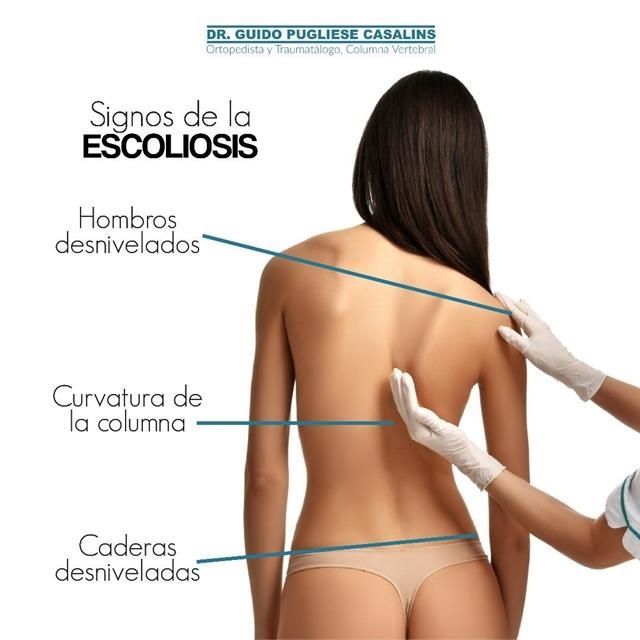

Ortopedista y traumatólogoOrtopedista de columna vertebralEscoliosis

Las especialidades de Dr. Guido Pugliese Casalins son: Ortopedista y traumatólogo, Ortopedista de columna vertebral, Escoliosis.

Presentaba una escoliosis desde niña que se me fue aumentando, apesar de que yo seguia todas las indicaciones de los medicos que me veian, progreso tanto que me daba pena usar ropa ajustada o vestido de baño. Otros medicos me decian que una cirugia era muy peligrosa porque podia quedar en silla re ruedas, y me recomendaron al Dr Guido una persona que habia operado de lo mismo, me anime y me someti a la cirugia. Desde ese dia mi vida cambio, me recupere rapidamente, hoy hago todas mis actividades normles y no me da pena ni usar vestido de baño. Gracias Dr Guido por cambiarme la vida !!!